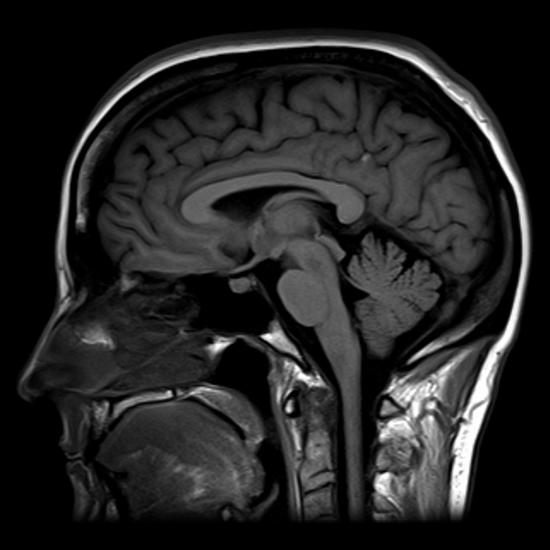

Magnetic resonance imaging (MRI) is a noninvasive medical imaging technique based on a phenomenon of nuclear physics discovered in the 1930s, in which matter exposed to magnetic fields and radio waves was found to emit radio signals. In 1970, a physician and researcher named Raymond Damadian noticed that malignant (cancerous) tissue gave off different signals than normal body tissue. He applied for a patent for the first MRI scanning device, which was in use clinically by the early 1980s. The early MRI scanners were crude, but advances in digital computing and electronics led to their advancement over any other technique for precise imaging, especially to discover tumors. The images created are really a set of hundreds of images that can be scrolled through section by section. To see this visualization visit Radiopedia.org and scroll up and down through the brain images related to this case - several views are available using different techniques and running in each of the three planes. MRI also has the major advantage of not exposing patients to radiation.

Drawbacks of MRI scans include their much higher cost, and patient discomfort with the procedure. The MRI scanner subjects the patient to such powerful electromagnets that the scan room must be shielded. The patient must be enclosed in a metal tube-like device for the duration of the scan (see Figure \(\PageIndex{2.b}\)), sometimes as long as thirty minutes, which can be uncomfortable and impractical for ill patients. The device is also so noisy that, even with earplugs, patients can become anxious or even fearful. These problems have been overcome somewhat with the development of “open” MRI scanning, which does not require the patient to be entirely enclosed in the metal tube. Patients with iron-containing metallic implants (internal sutures, some prosthetic devices, and so on) cannot undergo MRI scanning because it can dislodge these implants.

Functional MRIs (fMRIs), which detect the concentration of blood flow in certain parts of the body, are increasingly being used to study the activity in parts of the brain during various body activities. This has helped scientists learn more about the locations of different brain functions and more about brain abnormalities and diseases.